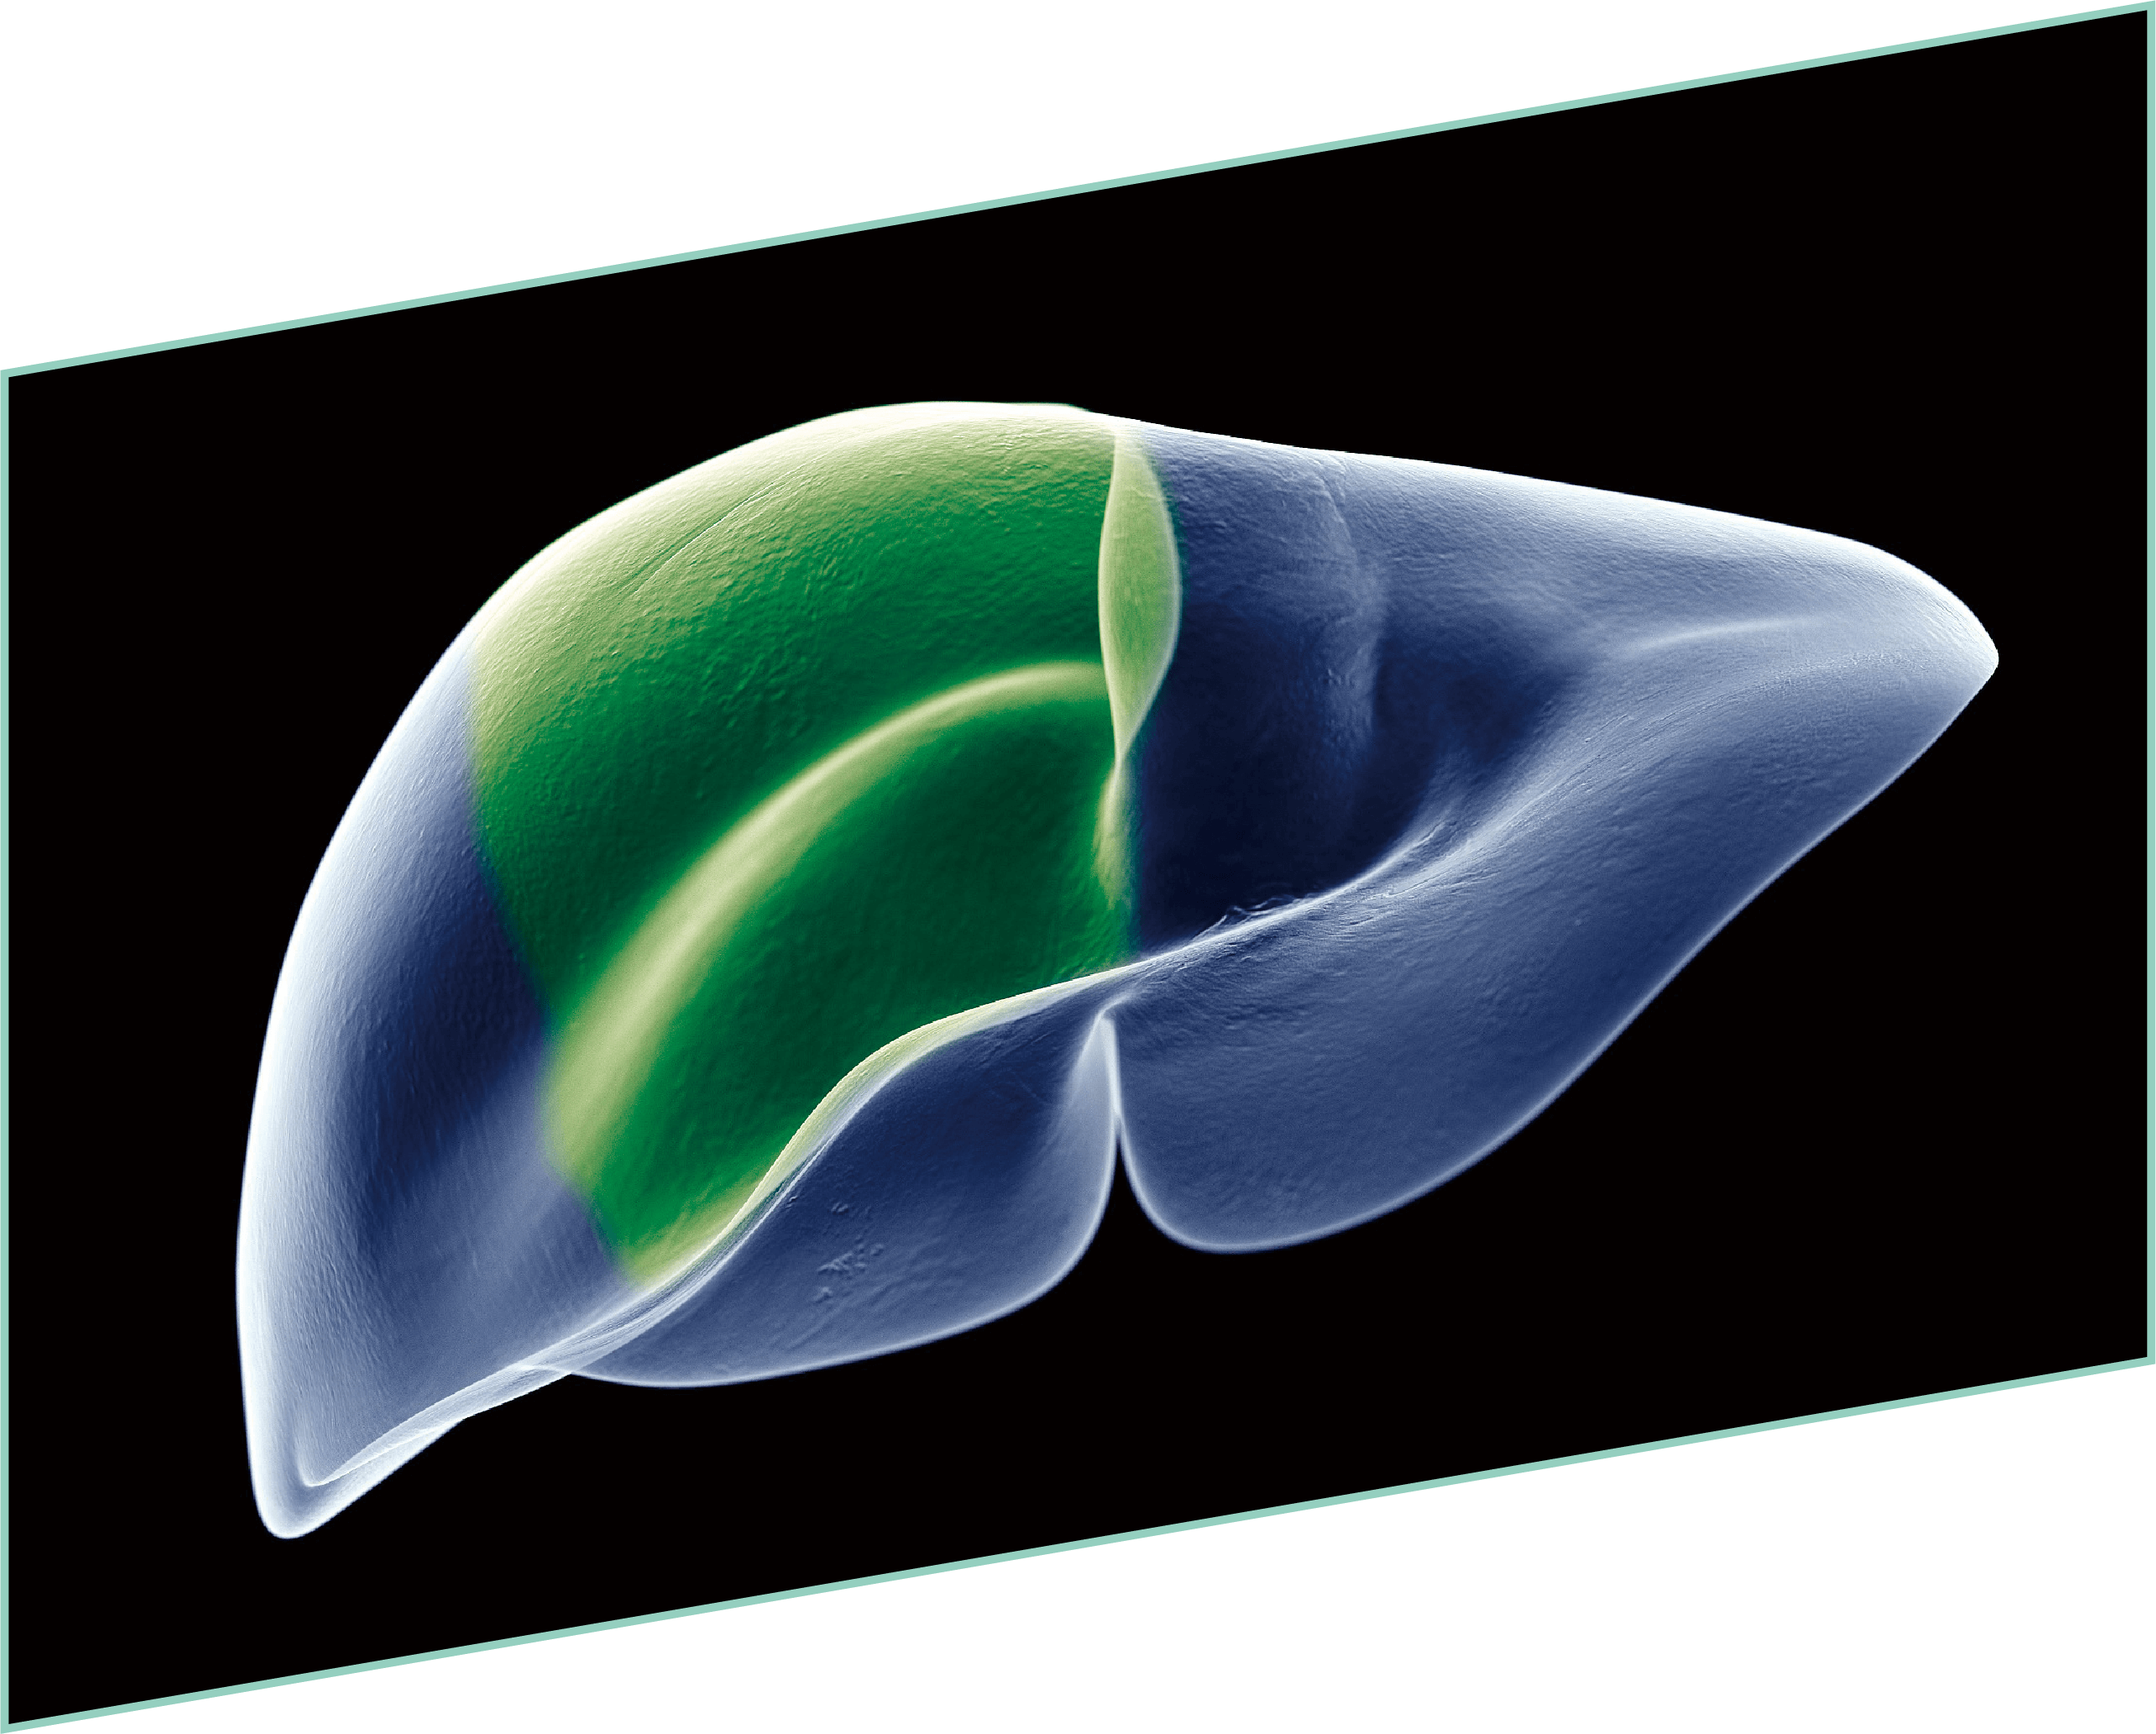

表面细节不遮盖

边界清晰,利于切缘评估

细微结构无伪影

避免术中误伤

荧光信号强弱分明

精准辅助临床决策

术中实时多维导航,领航诊疗一体新标准